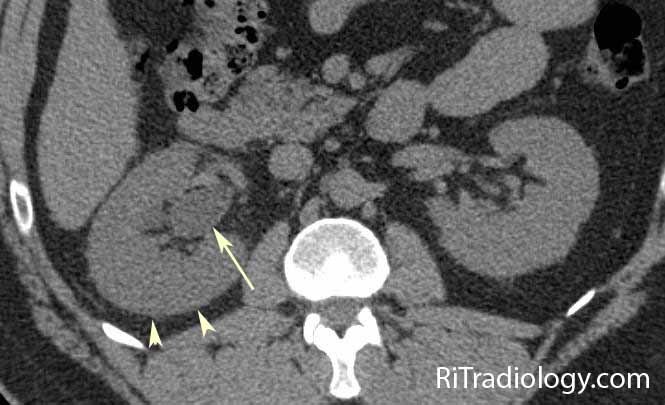

What do you see?

Mild enlargement of the right kidney, perinephric fat stranding on the right (sign of inflammation; arrowheads) and dilated right renal pelvis. Patient had ureteric stone.